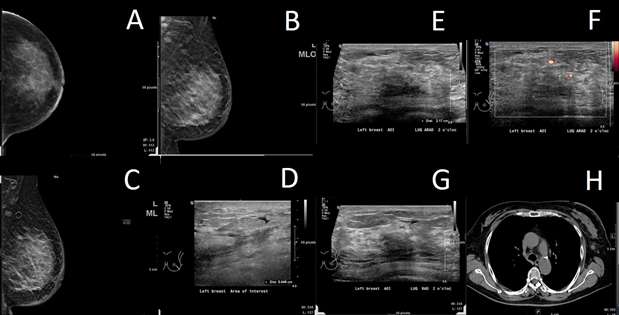

Breast metastasis from biopsy-proven ovarian carcinoma:

Case 2: